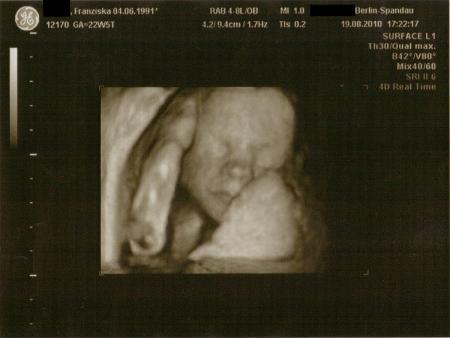

Und hier versteckt sie sich grad hinter ihrer Hand

Bild zu